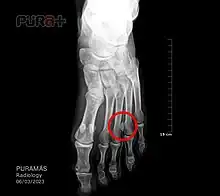

Though a neuroma is a soft-tissue abnormality and will not be visualized by standard radiographs, the first step in the assessment of forefoot pain is an X-ray to detect the presence of arthritis and exclude stress fractures/reactions and focal bone lesions, which may mimic the symptoms of a neuroma. Ultrasound (sonography) accurately demonstrates thickening of the interdigital nerve within the web space of greater than 3mm, diagnostic of a Morton's neuroma. This typically occurs at the level of the intermetatarsal ligament. Frequently, intermetatarsal bursitis coexists with the diagnosis. MRI can distinguish conditions that mimic the symptoms of Morton's neuroma, but when more than one abnormality exists, ultrasound has the added advantage of determining the precise source of the patient's pain by applying direct pressure with the probe. Ultrasound may also be used to guide treatment such as cortisone injections into the webspace, as well as alcohol ablation of the nerve.